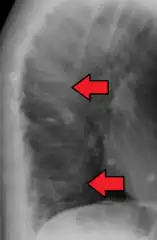

Compression fracture of the fourth lumbar vertebra post falling from a height.